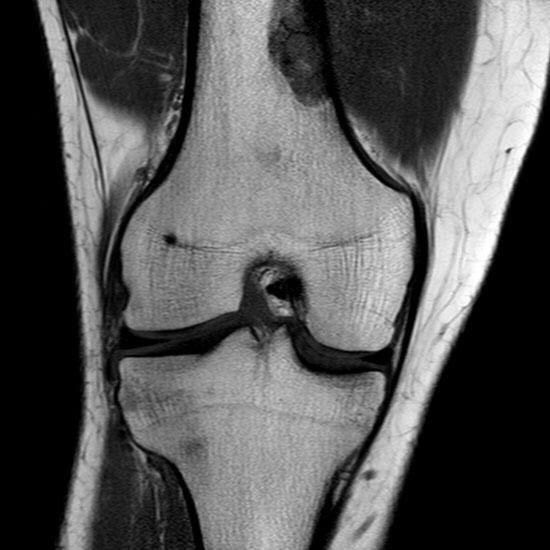

¿Cómo se ve el líquido sinovial en esta RM?

Image:

Carga móvil (image/jpeg)

Answer

Negro porque está ponederada en T1

Blanco porque está ponderada en T1

Negro porque está ponderada en T2

Blanco porque está ponderada en T2